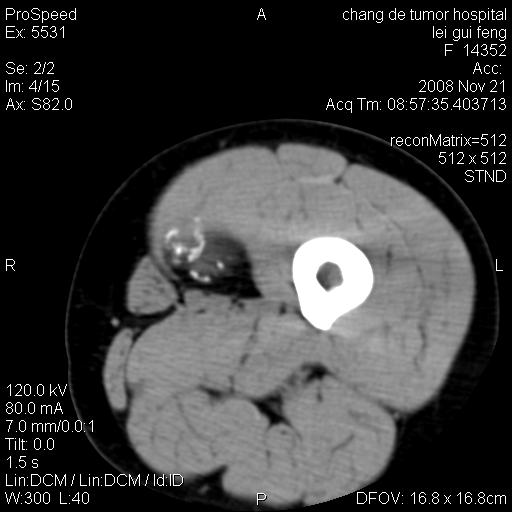

标题: CT16807:女 41 无不适 [打印本页]

标题: CT16807:女 41 无不适

考虑皮样囊肿可能性大

血管瘤可能

血管瘤

血管瘤可能性大!

黏液瘤或表皮杨囊肿

不排除横纹肌肉瘤可能。

血管瘤可能性大或畸胎瘤

考虑脂肪肉瘤

考虑血管瘤可能性大;不排除肉瘤可能。建议行活检。

脂肪肉瘤?

双是软组织肿瘤,病灶内多发钙化,另可见多量脂肪密度影,考虑畸胎瘤,血管瘤,不除外其他